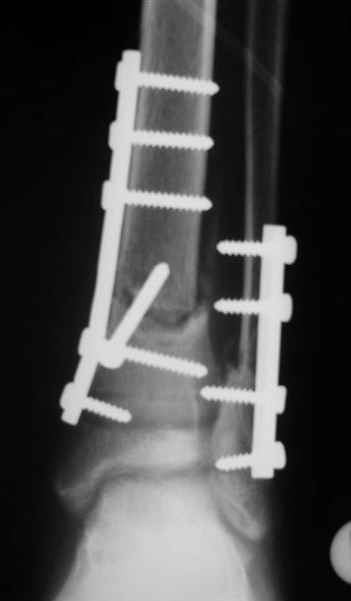

Уважаемый Виталий Евгеньевич,

Помятуя наш недавний разговор о фиксации м.б. кост, высылаю послеоперационные картинки..

Напомню- разбирали случай 17 летнего молодого человека перелом дист тиб.фиб. хирургия после 3 недель с момента травмы( безуспешные попытки закрытой репозиции) Раны заживают первичным натяжением, занимается физиотерапией, пока никаких проблем не наблюдается

Как ты тут оцениваешь восстановление оси большеберцовой кости?

Является ли рутинной практикой у вас использовать снимок противоположной конечности как шаблон для измерения осевых отклонений?

Согласный я с тобой:-)) есть остаточная вальгусная деформация (по снимку видно перекрывание дист. фрагментом б.б по латеральной поверхности проксимальноо фагмента на 2-3 мм и наружная лодыжка репонирована с укорочением, судя по прямой проекции. Необходимость использования интраоперационно дистрактора была бы оправдана (вручную было непросто *вытянуть* дистальный отломок.)

На мой взгляд, Ваша демонстрация неожиданно добавила перцу. Если память мне не изменяет, я говорил об отсутствии показаний к остеосинтезу малоберцовой.

Сейчас можно заикнуться о вредности этой манипуляции с точки зрения риска фиксации в неправильном положении, как это получилось у Вашего пациента. Сначала фиксировали большеберцовую, и надо было на этом остановиться, ин май хамбл опиньон. Потом при закручивании винтов на мощнейшей второй пластине сустав увело на вальгус. С учетом того, что пацану всего 17, я бы удалил пластину с малоберцовой и попытался тем или иным способом устранить смещение, пока не срослось.